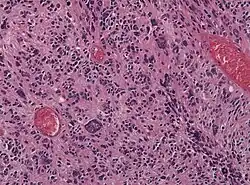

![]() | Tumor giant cell | Malignant neoplasm showing marked anaplasia. Note the marked nuclear pleomorphism, bizarre cells and tumor giant cells. | Category: Histopathology of giant cell tumors | Giant cell tumor |